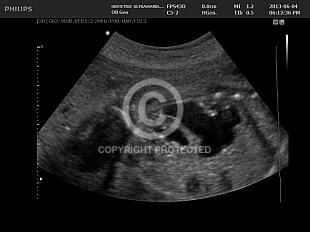

Ureterocele

Other kidney anomalies

Fetal Hydronephrosis

Hydronephrotic upper pole of duplex kidney

Solitary renal cyst and abnormally homogenous renal tissue

Fetal Cystic Kidneys

Double renal pelvis and ureterocele